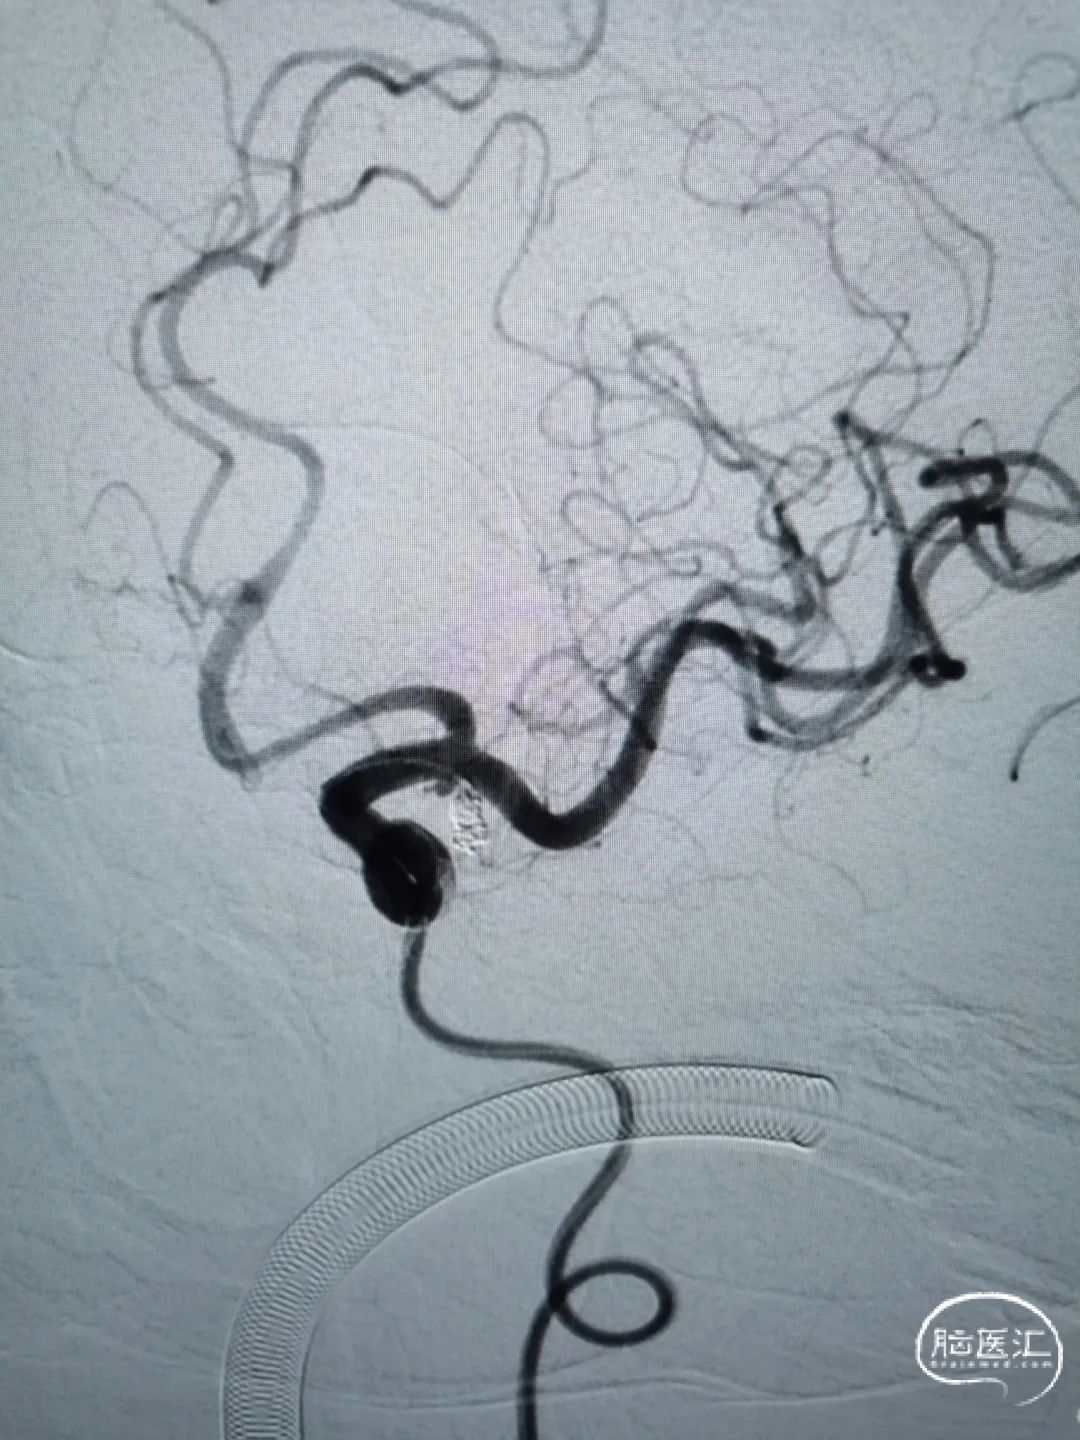

DSA造影提示主动脉III型弓,左侧颈内动脉迂曲明显,远端血管通畅。

左侧大脑中动脉M1段起始处动脉瘤,大小2.3mm*4.8mm,瘤颈宽1.4mm。主动脉III型弓,左侧颈内动脉血管非常迂曲,患者血管条件较差。

术后即刻造影

动脉瘤栓塞满意,Raymond分级I级。左侧颈内动脉正侧位造影提示血管显影良好,未见血管痉挛等。